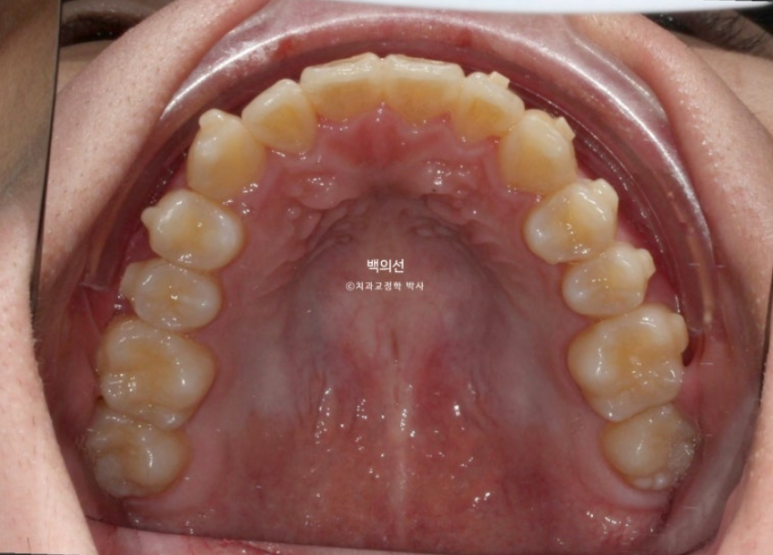

송곳니 덧니가 있고 덧니 옆 앞니는 입천장으로 나서 아랫니가 거꾸로 물리는 반대교합 입니다.

교합이 뜨는 부분들이 있습니다.

어금니 교합은 좋고 돌출이 없어서 치간삭제 소량 동반한 인비절라인 라이트 권유드렸습니다.

24.12

배열도 완벽 합니다.